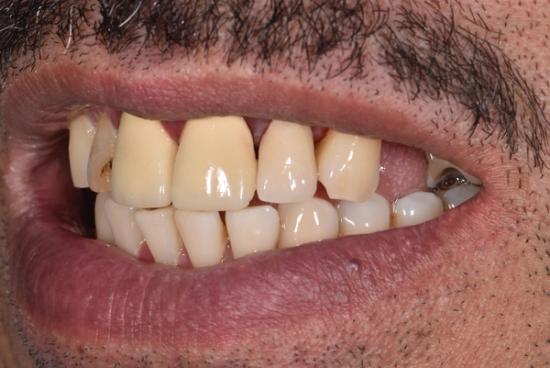

After Photo